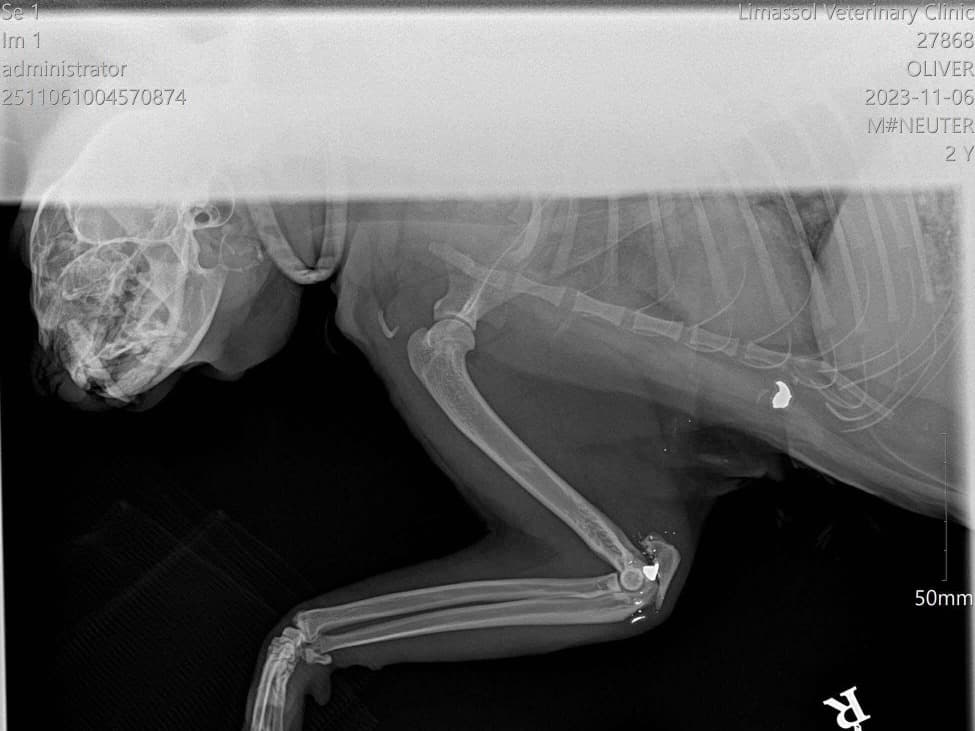

Oliver was hit by a car on the highway near Parekklisia. His pelvis was shattered. After surgery and months of recovery at the sanctuary, he fought hard. Oliver passed away in January 2026. He was the most affectionate cat at the sanctuary — he'd curl up in your lap and purr for hours. He never stopped trusting people, even after everything. Oliver is why we do this.